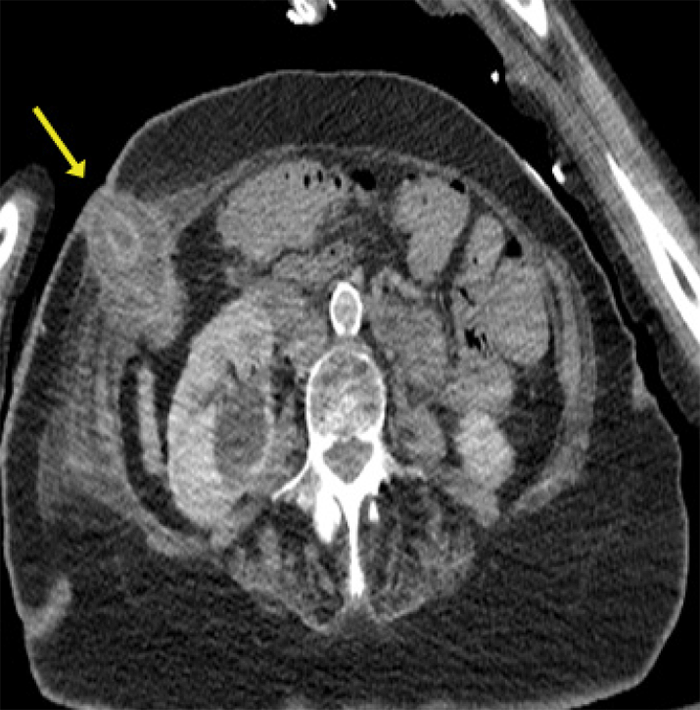

All of her blood tests, including complete blood count, electrolytes, renal function, bilirubin, and liver function, were normal. A computerized tomography (CT) scan with oral Gastrografin and intravenous Isovue contrast was performed, which showed gallbladder herniation through a defect in the anterior abdominal wall immediately beneath the rib cage in the anterior lateral wall. Additionally, there was a track extending inferiorly from the herniated gallbladder, suggestive of a cholecystocutaneous fistula (Figure 3). The patient's abdominal pain was colicky in nature, prompting us to dislodge the impacted stone from her cholecystocutaneous fistula manually, which provided immediate relief of the patient's abdominal pain. The dislodged gallstone was collected and measured 4 cm × 4 cm.

Figure 3. Axial View of CT Angiogram Demonstrating Gallbladder Herniation Through Abdominal Wall. Published with Permission